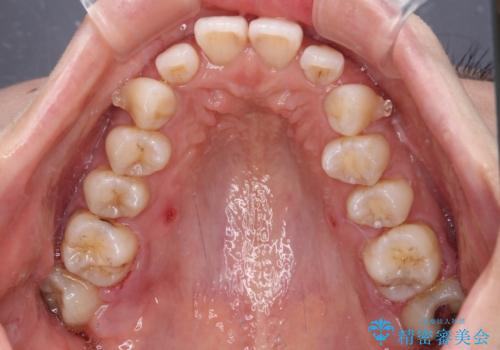

- デコボコと飛び出している前歯を気にして来院された患者様です。

歯列としてはインビザラインでもワイヤー矯正でも対応できるものでしたが、奥歯の咬み合わせを見た時に上顎がやや前方にあり、インビザライン単独では時間のかかってしまう可能性があるため、補助装置を治療当初に使用することで、インビザラインによる治療をスムーズに行えるように計画しました。